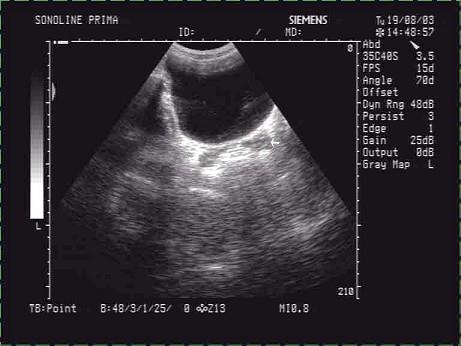

问题 超声检查中,一男患者中下腹横切面如图,箭头所示器官为?(?)

选项 A.前列腺 B.淋巴结 C.精囊腺 D.睾丸 E.肠管

答案 C